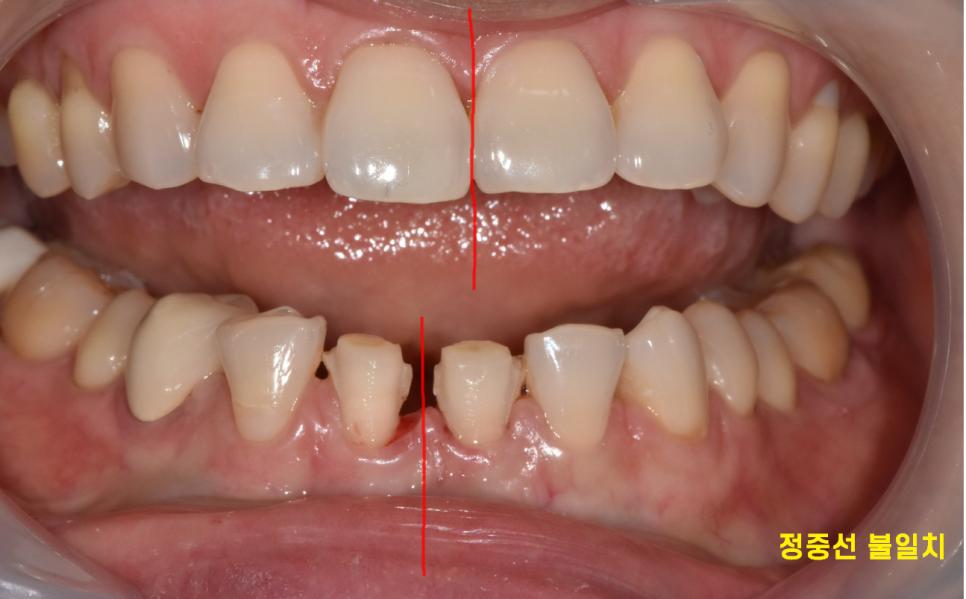

230523

환자분은 치아의 가운데 선

정중선이 어긋난 안면 비대칭 상황이었습니다.

보철로도 맞출 수 없다는 것을 인지 후

라미네이트를 제작해드렸습니다.